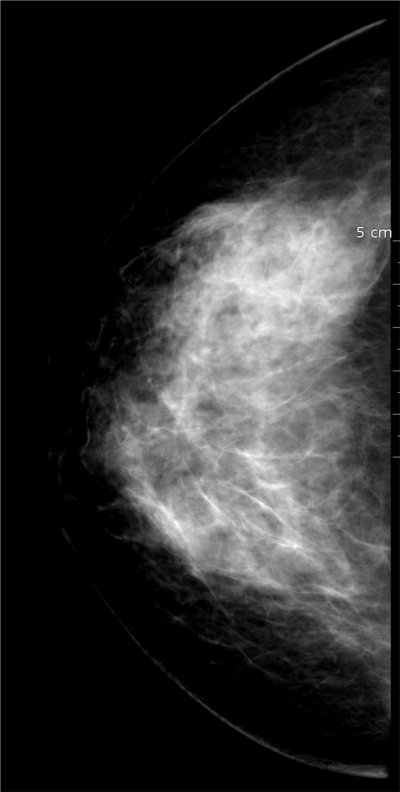

Mammotome biopsies du sein

nous sommes également là pour la prise en charge des actes interventionelles sur le sein.